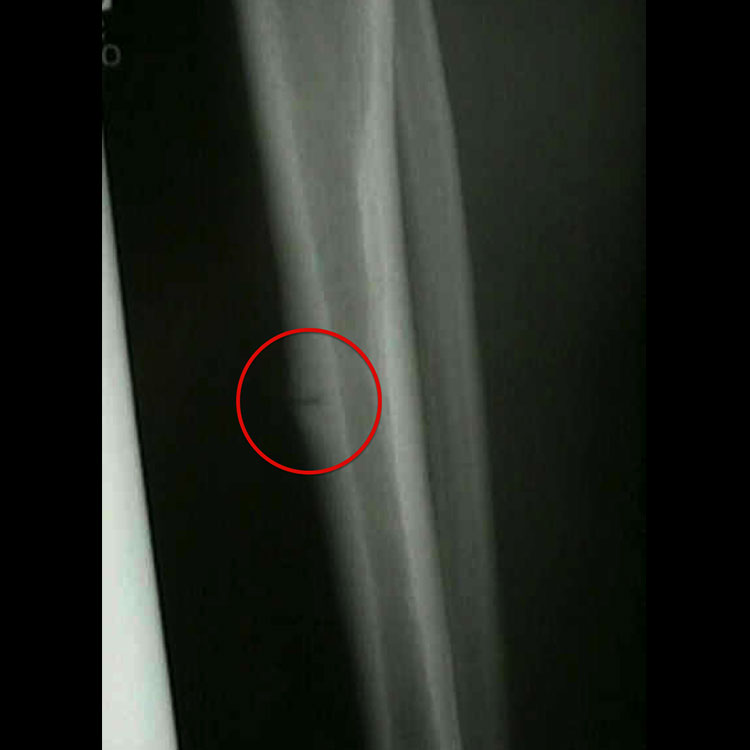

전방 경골 (Anterior tibia): 진단 후 모든 고충격 활동을 최대 3개월 동안 피해야 합니다. 치유에 최대 6개월이 걸릴 수 있으며, 저강도 펄스 초음파(LIPUS)가 골 치유에 도움을 줄 수 있습니다. 외과적 치료는 골수내정 고정술 또는 전방 인장 밴드 플레이팅 등이 고려될 수 있습니다.